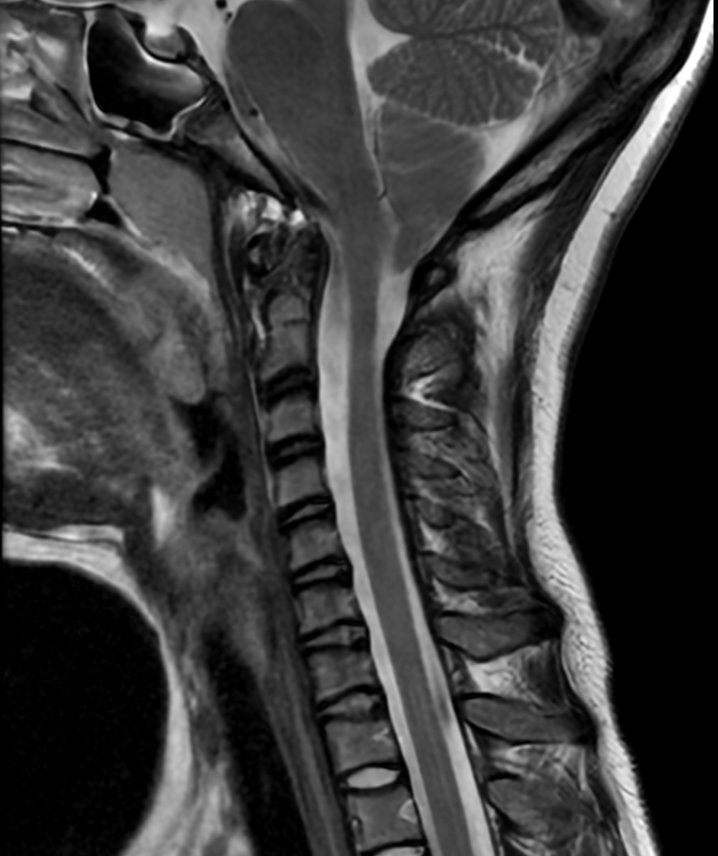

Boyun Düzleşmesi

Boyun Düzleşmesi Belirtileri Nelerdir?

Boyun düzleşmesi, omurganın doğal eğrisinin bozulması nedeniyle çeşitli fiziksel rahatsızlıklara yol açabilir. Bu belirtiler genellikle boyun ve çevresindeki yapılar üzerinde artan yük, sinir baskısı ve kas gerginliği sonucunda ortaya çıkar. İşte boyun düzleşmesinin en sık görülen belirtileri:

Boyun düzleşmesi olan kişilerde en yaygın şikayet boyun bölgesindeki sürekli ağrıdır. Bu ağrı, genellikle gün boyunca artar ve uzun süre aynı pozisyonda kalma veya boynu zorlayan aktivitelerle daha belirgin hale gelir.

Omurga hizasının değişmesi, omuz ve sırt bölgesine ek yük bindirir. Bu durum, özellikle kürek kemiği çevresinde yoğun bir ağrı hissine yol açabilir.

Boyun kaslarının gerginliği ve servikal sinirler üzerindeki baskı, genellikle gerilim tipi baş ağrılarına neden olur. Bu ağrılar, ense kökünden başlar ve başın ön kısmına kadar yayılabilir.

Boynun doğal eğriliğinin kaybolması, hareket kabiliyetini kısıtlar ve boyunda sertlik hissine neden olur. Bu durum, boynu sağa, sola, öne veya arkaya çevirme gibi temel hareketleri zorlaştırabilir.

Boyun düzleşmesi, omurilikten çıkan sinir kökleri üzerinde baskıya neden olabilir. Bu baskı sonucunda, genellikle kollar ve ellerde uyuşma, karıncalanma veya elektrik çarpması benzeri hisler görülebilir.

Boyun düzleşmesi, servikal omurgadaki yapılarla bağlantılı olan denge mekanizmasını etkileyebilir. Bu durum, baş dönmesi ve dengesizlik gibi şikayetlere yol açabilir.

Boyun ve çevresindeki kaslar, omurganın doğal duruşunu koruyabilmek için aşırı çalışabilir. Bu durum, kronik kas gerginliğine ve zaman zaman kas spazmlarına neden olabilir.

Omurganın doğal dengesi bozulduğunda, vücut bu durumu telafi etmek için ekstra enerji harcar. Bu, genel bir halsizlik ve yorgunluk hissi yaratabilir.

Boyun düzleşmesi, vücudun genel duruşunu da etkileyebilir. Kamburluk veya omuzların öne doğru eğilmesi gibi postür bozuklukları görülebilir.

Boyun düzleşmesi belirtileri, genellikle kişinin yaşam kalitesini düşürür ve günlük aktivitelerini kısıtlar. Eğer bu belirtilerden biri veya birkaçı sizde mevcutsa, erken dönemde bir fizik tedavi uzmanına ya da ortopedi doktoruna başvurmanız önemlidir. Erken teşhis ve doğru tedavi ile belirtiler hafifletilebilir ve ilerlemesi önlenebilir.